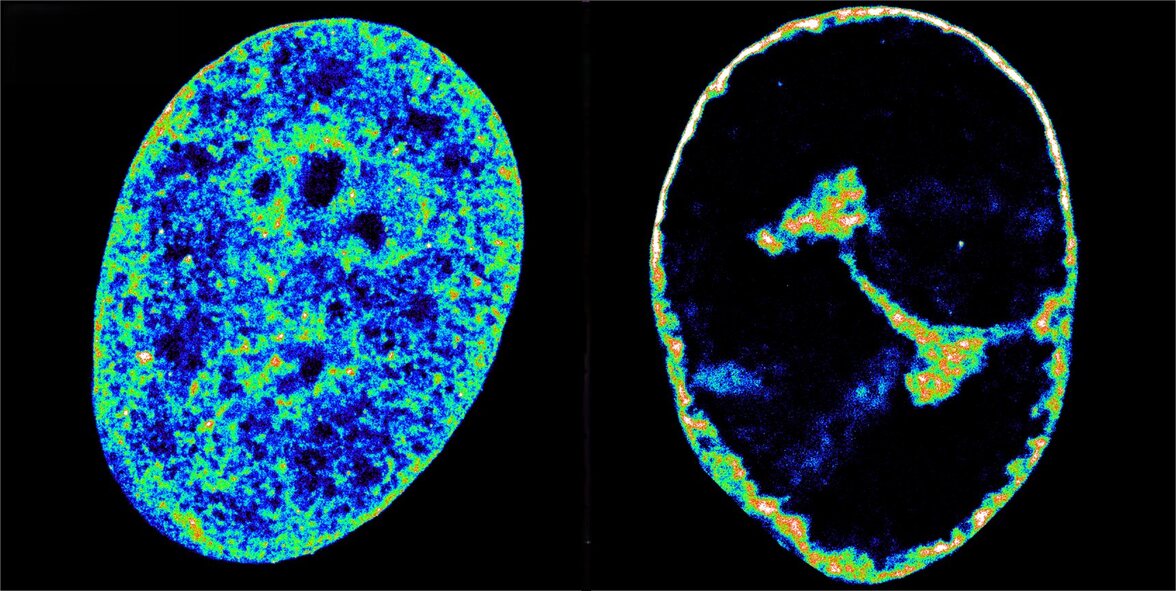

Ученые обнаружили, что враждебный захват начинается в течение первого часа, когда вирус захватывает фермент РНК-полимеразу II человека, чтобы помочь синтезировать собственные белки. Топоизомераза I, фермент, который расщепляет ДНК и структурный белок когезин последовали за человеческой РНК-полимеразой II во вновь формирующиеся участки репликации вируса. Через три часа после заражения большая часть полимеразы и значительная часть двух других факторов покинули человеческие гены. Массовая кража приводит к нарушению транскрипции во всем геноме хозяина, что, в свою очередь, приводит к тому, что хроматин, естественное состояние человеческого генома внутри клеток, сжимается в плотную оболочку, составляющую всего 30% от его первоначального объема (см.фото).

Это было неожиданное открытие, поскольку считается, что структура хроматина определяет транскрипцию. "Мы всегда думали, что плотный хроматин блокирует работу генов, но здесь мы видим обратное: сначала прекращается транскрипция, а затем ДНК уплотняется. Взаимосвязь между активностью и структурой может быть улицей с двусторонним движением", - отмечает Альмела.